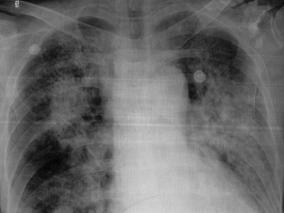

1小时条评论患者男性,75岁,于2008年4月15日入院。 一、主诉 急性阑尾炎术后第二天,突发呼吸困难2小时。 二、病史询问 (一)初步诊断思路及问诊目的 患者为老年男性,急性阑尾炎术后,急性起病,以呼吸困难为突出的临床表现而请求会诊。首先想到的是患者的呼吸困难是心...